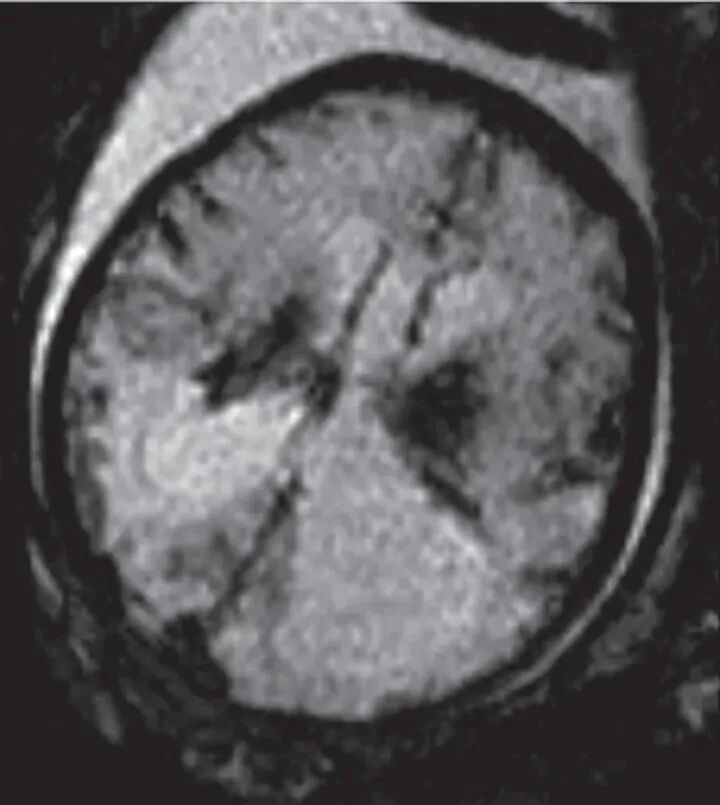

随后行MRI检查显示尾状核丘脑沟异常信号,脑室周围白质广泛水肿样改变(图3),胎儿大头畸形及肝脾大。